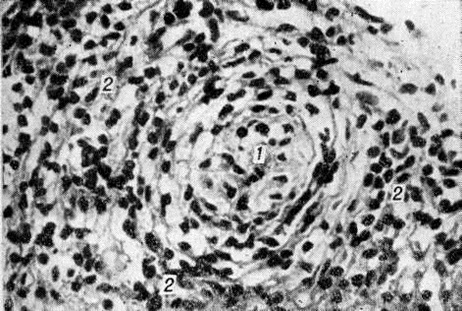

Морфологически структуры, содержащие элементы, характерные для обоих типов Лепра и являющиеся как бы переходной стадией между полярными типами, характерны для пограничной Лепра При недифференцированной Лепра наблюдается картина банального хронический воспаления (смотри полный свод знаний) без специфических изменений. Основными гистологический критериями, определяющими принадлежность к классификационным группам Ридли — Джоплинга, являются следующие морфологический особенности инфильтрата. 1. Клеточный состав гранулемы. В верхней половине спектра (ТТ, ВТ и ВВ) характерно наличие эпителиоидных клеток (цветной рисунок 8) и для ТТ — многоядерных (гигантских) клеток типа Лангханса (цветной рисунок 9). При ВВ эпителиоидные клетки часто отделены друг от друга отёком. В нижней части спектра (BL и LL) эпителиоидные клетки уступают место макрофагам, цитоплазма которых по мере приближения к типу LL становится более плотной, пенистой и содержит жир. 2. Плотность популяций микобактерий. Количество микобактерий возрастает пропорционально от верхней части спектра к нижней. В числовом выражении показатель бактериальной насыщенности лепроматозного инфильтрата для ТТ, ВТ, ВВ, BL и LL составляет 0/1; 0/2,5; 3/4,5; 4/5,5; 5/6,5 соответственно. 3. Количество и топография лимфоцитов в гранулеме. Для ТТ и ВТ свойственно высокое содержание лимфоцитов, расположенных в виде плотного бордюра вокруг массы эпителиоидных клеток. При ВВ и LL количество лимфоцитов чаще снижено, они рассеяны по гранулеме и не образуют вала. 4. Поражение кожных нервов. Для туберкулоидной части спектра характерно значительное утолщение нерва за счёт массивного инфильтрата (повышение максимального диаметра пучка при ТТ). Для ВВ и BL патогномоничны изменения периневрия в виде луковичной кожуры (onion skin) за счёт расслоения его инфильтратом из лимфоцитов, плазмоцитов (при В В) или бактериосодержащих макрофагов (при BL). 5. Отношение к эпидермису. При ТТ и ВТ гранулема располагается непосредственно под эпидермисом и может эрозировать его. При ВВ, BL и LL между инфильтратом и эпидермисом постоянно остаётся непоражённая зона толщиной 30 — 75 микрометров — так называемый слой Ипа, состоящий из коллагеновой ткани.

Для Лепра характерно поражение периферической нервной системы. Микобактерии обнаруживаются практически во всех участках нервных волокон. При лепроматозном типе инфильтрат состоит из пенистых макрофагов, при туберкулоидном — из эпителиоидных клеток. Отмечается более быстрое развитие воспаления при туберкулоидном типе, чем объясняется раннее появление неврологический нарушений. При лепроматозном типе Лепра происходит постепенное замещение нервного волокна соединительной тканью. Лепрозный неврит, как правило, имеет восходящий характер. Отмечается наиболее частое поражение чувствительных нервов и выраженный тропизм микобактерий Лепра к леммоцитам (шванновским клеткам).